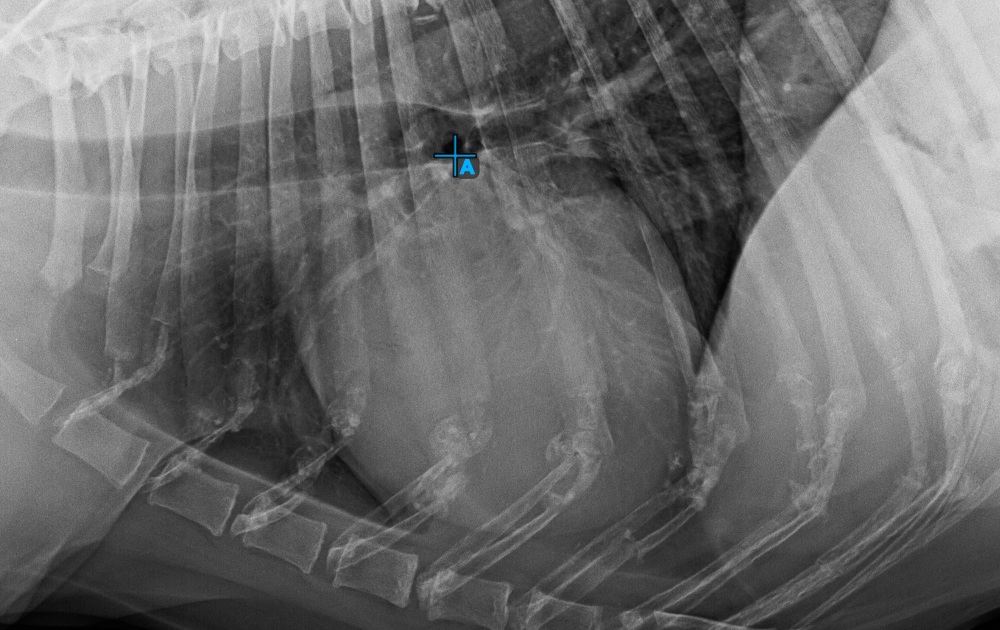

Start the measurement by marking the Bifurcatio tracheae, near the top of the heart.

The image below represents a typical placement of the Bifurcatio tracheae point.